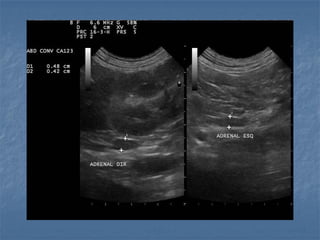

Hiperplasia adrenal bilateral

 Hiperadrenocorticismo  Hipofisáriodependente: há um aumento bilateral (80% dos casos!), pode ser simétrico ou assimétrico * Medida normal de espessura menor que 0,74cm cães adultos